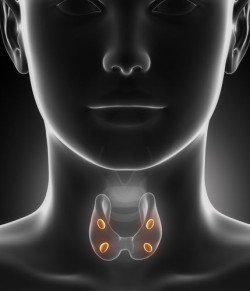

Onglyza Thyroid Cancer

Onglyza thyroid cancer, for instance, is a slow-growing cancer that can take many years to develop, and may only be discovered in the later (and more dangerous) stages.

The FDA has already received dozens of reports regarding Onglyza thyroid cancer from patients taking Ongluza and other similar drugs.

Reports such as these do not definitively prove a link between Onglyza and thyroid cancer, but they are cause for concern.

Thyroid Cancer Symptoms

It is important to recognize thyroid cancer symptoms, especially for users of Onglyza, or a similar incretin mimetic drug, in which thyroid cancer may be a potential side effect.

Thyroid cancer symptoms include:

- Changes in voice

- Neck swelling

- Respiratory problems

- Difficulty swallowing

- Lymph nodes that are enlarged or painful

- Lumps or nodules on the lower front or center of the neck

- Coughing or hoarseness that is unexplained

While these may not seem like serious symptoms, Onglyza patients especially should be aware that these may indicate thyroid cancer and be especially cautious.